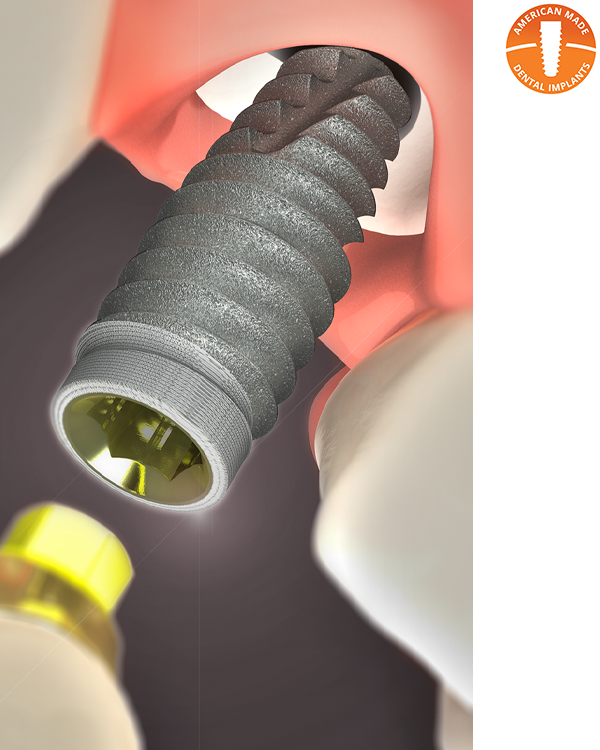

Observe 2–3 live implant surgeries showcasing immediate placement techniques in various sites using smart shape healing abutments.

Immediate implant placement offers significant clinical and operational advantages for both specialists and general dentists—especially when paired with smart shape healing abutments that support efficient healing and streamlined workflows. This course provides clinicians with the skills and knowledge to confidently plan, place, and restore immediate implants using a fully digital approach from assessment through final prosthetic delivery. Participants will explore case selection criteria, risk factors, and complication prevention strategies while gaining insight into the biological benefits of smart shape healing abutments. The program features a blend of lecture, workflow analysis, hands-on intraoral scanning, and 2–3 live surgeries demonstrating implant techniques across various clinical scenarios. By the end of the course, attendees will be equipped to integrate immediate implant placement into their practice with confidence—enhancing patient outcomes, clinical efficiency, and treatment success through modern digital protocols.

Gain the confidence to place immediate implants with precision using smart shape healing abutments and digital workflows. This immersive course offers the live training and hands-on experience you need to deliver efficient, predictable results and elevate patient care.